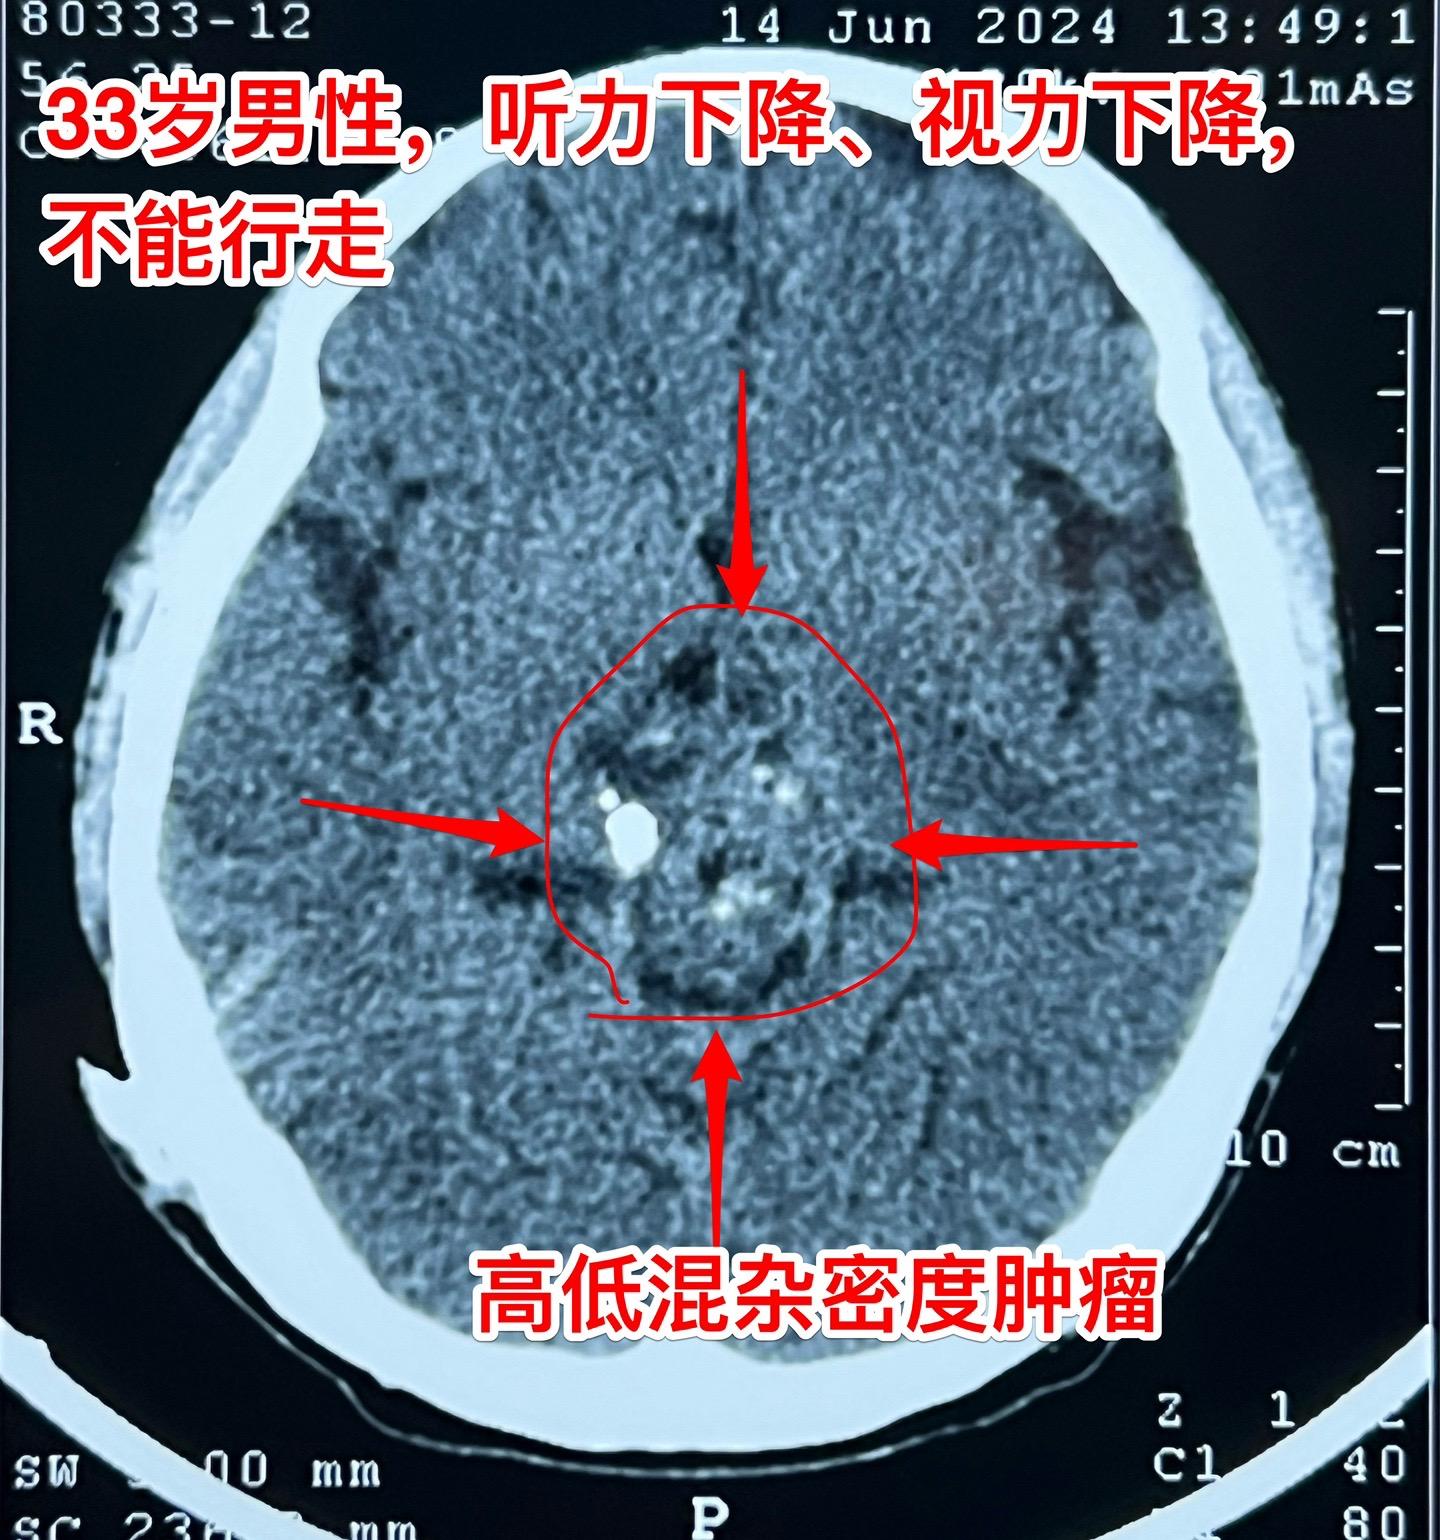

33岁贵州男性,脑部畸胎瘤。33岁贵州男性,病史11年。 11年前因多饮多尿在北京市某医院按生殖细胞瘤行全脑放疗,之后症状好转,能工作。 近两个月他记忆力差、爱睡觉、听力下降、视力下降。脑部磁共振显示松果体区肿瘤,在北京市某医院行肿瘤穿刺活检术,病理报告结果考虑是乳头型颅咽管瘤(活检标本标注为鞍区占位,可能误导了病理科医生,见图6)。 放疗医生及化疗医生说根据这个病理 结果是不敢实施放疗和化疗的。神经外科医生说开颅切除肿瘤风险非常大。 处于绝